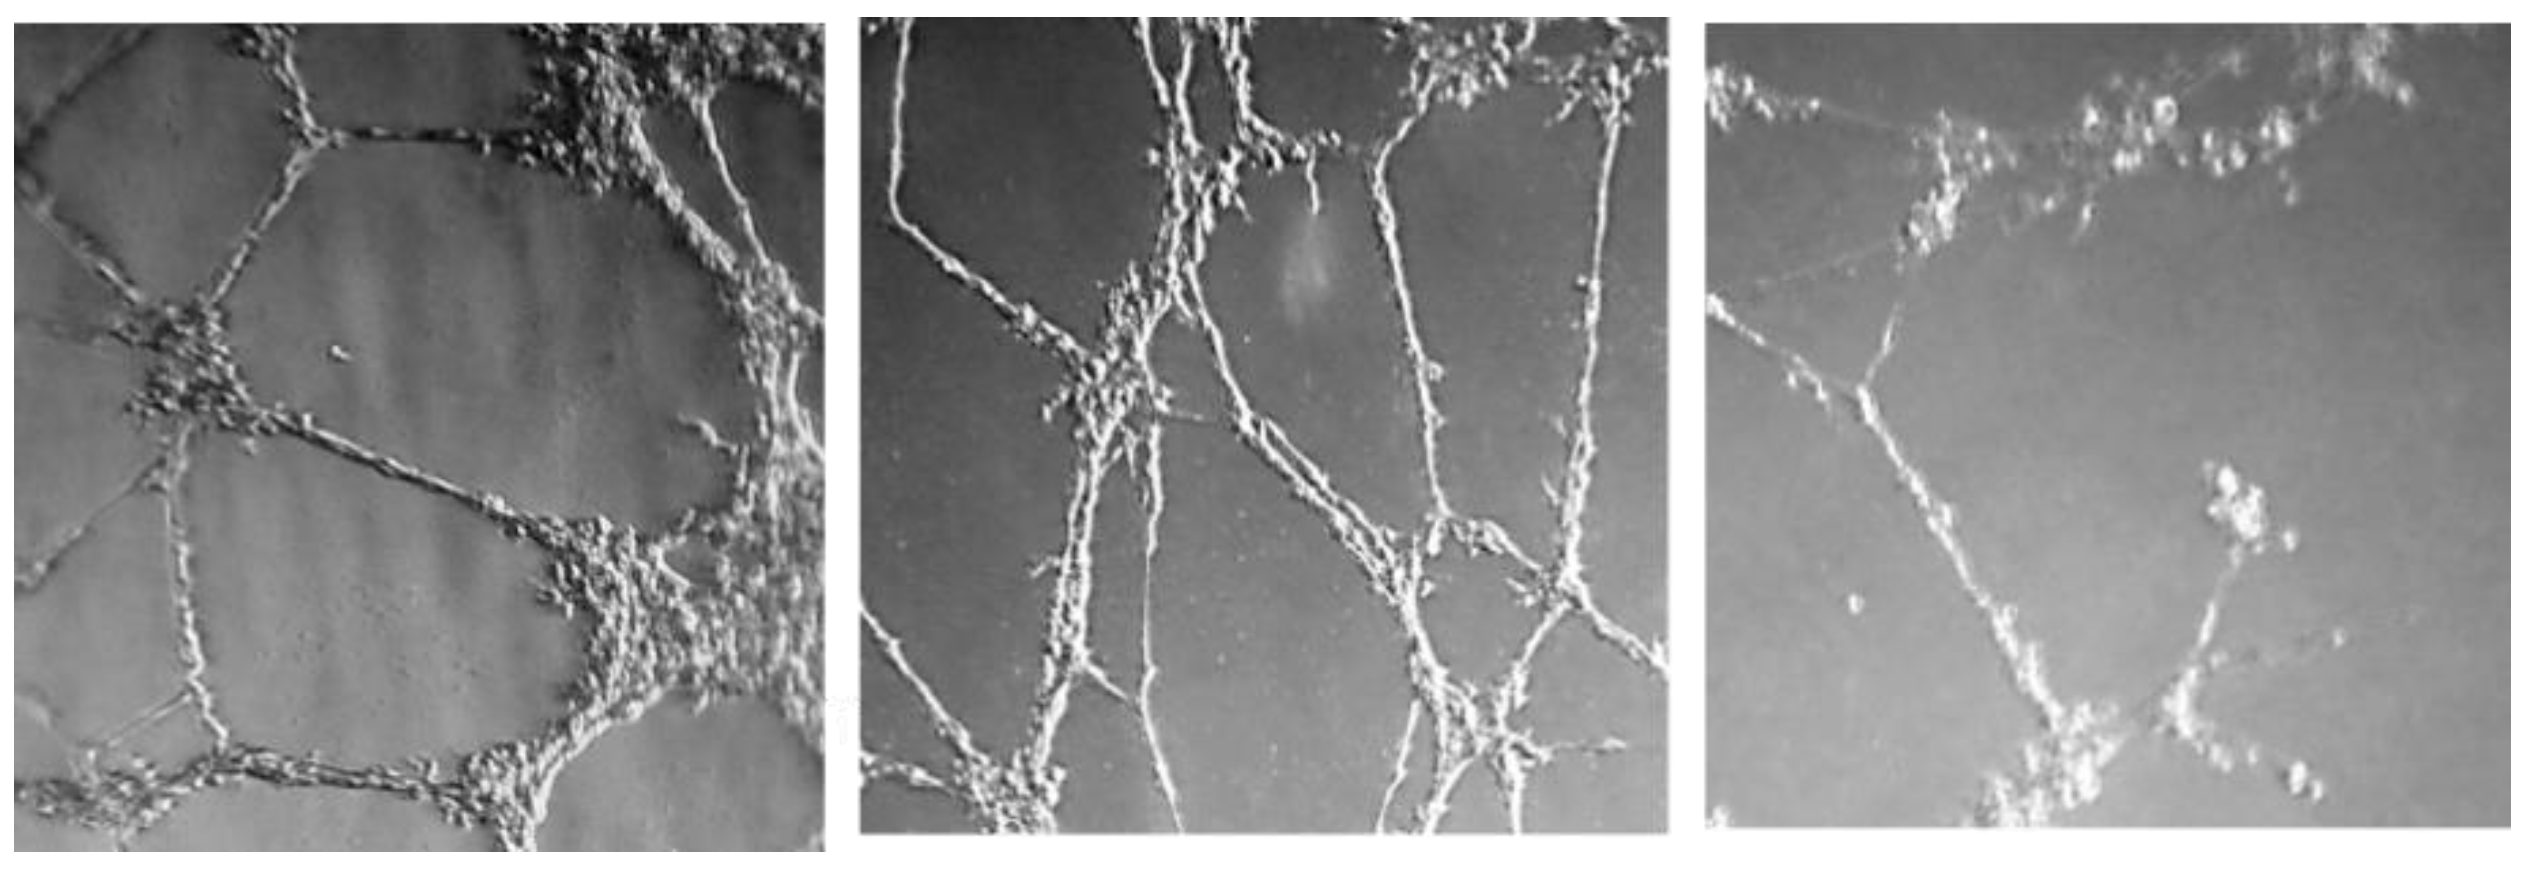

2.2.3. Effect on Microtube Formation on Endothelial Cells

| Comp. | Minimum Active Conc. (µM) |

|---|---|

| Sunitinib | 3 |

| Sorafenib | 10 |

| 16 | 10 |

| 23 | 1 |

| 33 | 6 |